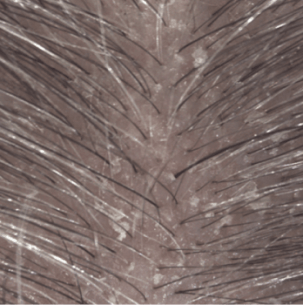

Résultats d'efficacité

Induration à 1 mois (3)

Amélioration de la qualité de vie (4)

(1) Etude clinique auprès de 54 sujets présentant un psoriasis du cuir chevelu léger à modéré. Phase d’attaque de 4 semaines : 3 shampoings par semaine.

(3) Évaluation clinique de l’induration des plaques à J29.

(4) Score DLQI à J29.